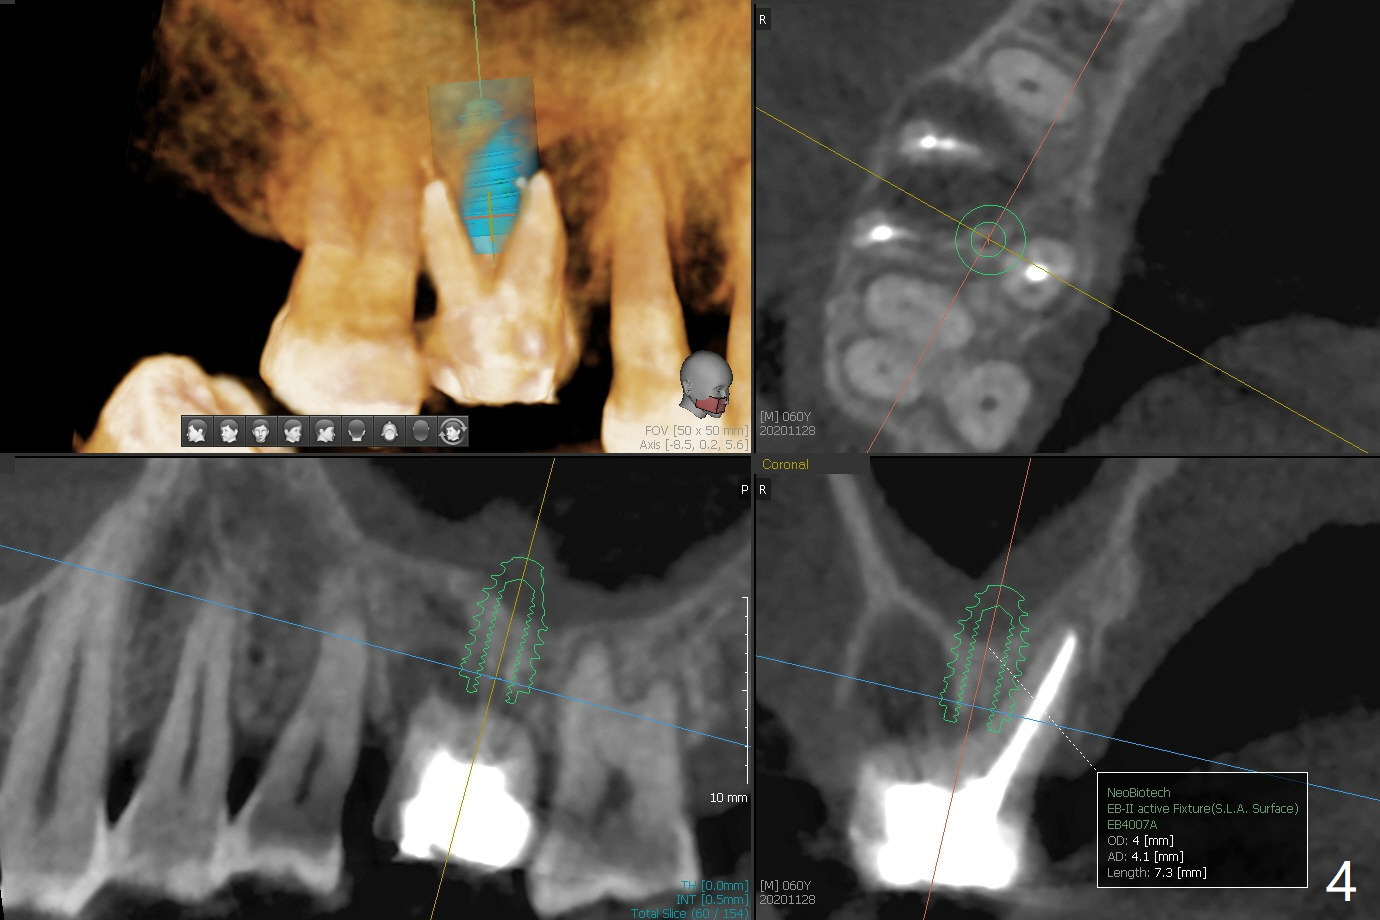

60岁男右上6出现脓包(图一),颊侧牙周袋深9毫米,指向近中颊侧根尖,根尖片(图二)和CT(图三(去除牙冠后))显示巨大近中颊侧根周骨质吸收,但是松动度低,一度想做根切。最佳植牙位点偏远中腭侧(图四),植体偏小,稳定性差,使用临时基台制作牙合面低的临时牙冠,目的包括固定粘性骨粉和防止邻牙移位。半张PRF膜用于上颌窦提升,另外半张用于覆盖牙槽窝开口的骨粉。局部使用抗菌素(Arestin),十九天后瘘道消失,根切,植骨可能成功。